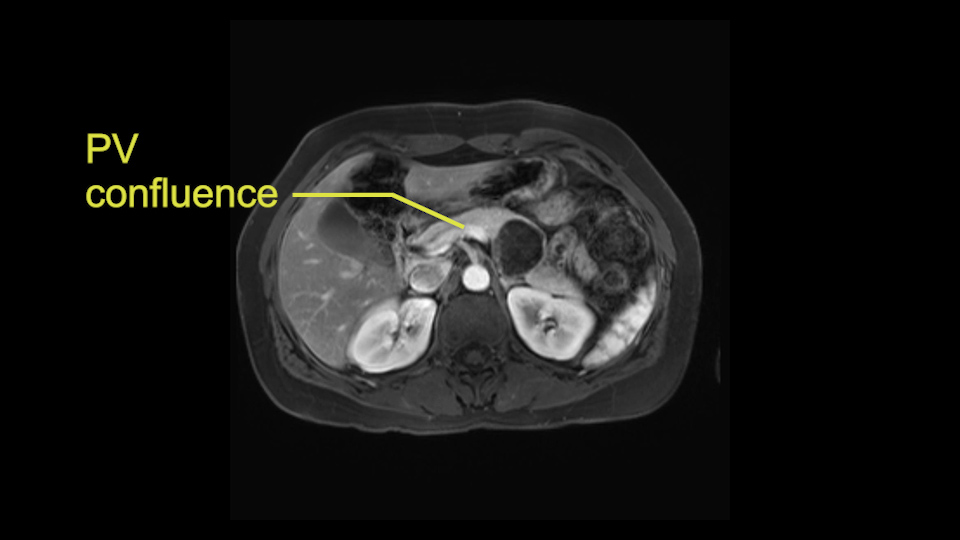

The slowing down moments or considerations that I give when I look at the scan and plan my distal pancreatectomy is how far away the tumor is to the portal vein and do I have to formally create a tunnel behind the pancreas on top of the portal vein or do I have to take the pancreas further to the left of the portal vein or the patient’s left of the portal vein. So here I can see that here is the tumor here. I can see that the tumor is a fair way away to the patient’s right and so I will likely not have to take or create the tunnel formally in this procedure. And that speaks a lot to the resection margins. So its important when you’re doing a distal pancreatectomy or any procedure potentially for oncologic reasons to get clearance of the tumor and to take the tumor kind of intact.

Key features that I look at the imaging are: first I look at the distance between the cyst and the portal vein SMV confluence. So there are guidelines for this, they call the Yonsei guidelines, to decide to do it laparoscopically or open and basically it says that if it’s a cancer, at least a centimeter away from the celiac trunk or the venous confluence. This is a cyst. So maybe you could stretch that a bit, but you don't want to get into trouble there. So for this cyst if you look at it, it's nicely away from the confluence.

So unfortunately I cannot show you a coronal view but you can see it easily on this scan, going down first you see the celiac trunk and you see here, quite a nice distance between the celiac trunk and the beginning of the mucinous cyst. And if you go up here and follow down the portal vein confluence you also see a nice distance there.

So what I would normally do in these patients, I would look at the abutment of any other organs, one, which is here, potentially the adrenal gland and two the small bowel. And two, look at the distance from the vessels which I would normally do in a coronal view. So you can easily measure the distance and third I look at the insertion of the inferior mesenteric vein. Now we can probably also see that on here. Although it's better on a CT scan and it's better on a coronal view, you want to know where the inferior mesenteric vein comes into either the splenic or the SMV, because that is typically a very important slow down moment when you mobilize the lower portion of the pancreas knowing where the inferior mesenteric vein comes in either the splenic vein or the SMV. So those are I think the three most important points for the CT scan.